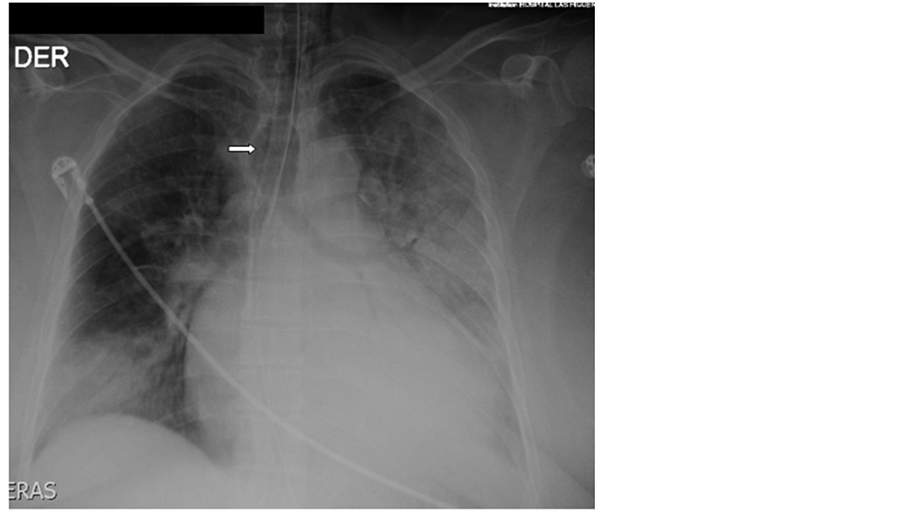

A 52 years old morbid obese lady consults at the Emergency Department of our Hospital with severe Community Acquired Pneumonia in respiratory failure with a Pa02/Fi02 ratio of 120 and obtunded, requiring immediate orotracheal intubation and connection to invasive ventilation. Tracheal intubation was difficult because of extreme obesity, shortness of neck and psychomotor agitation. Immediately after connection to a ventilator programmed with protector ventilation parameters progressive subcutaneous emphysema at the cervical region appeared. The patient evolved initially with arterial hypotension needing vasoactive drugs. The X-ray of thorax aroused the suspicion of overinflation of cuff (Figure 1) and the Computed Tomography of thorax (CT) of thorax depicted lost of continuity of the distal membranous wall of the trachea with air leak into the mediastinum (Figure 2). Bronchoscopy showed a large 4 cm rupture of the posterior wall of the trachea with protrusion of anterior wall of the esophagus into the tracheal lumen (Figure 3(a)). Broad spectrum antibiotic regime was started (ertapenem).

Figure 1. X-ray showing multifocal pneumonia and overinflated endotracheal tube cuff (arrow).